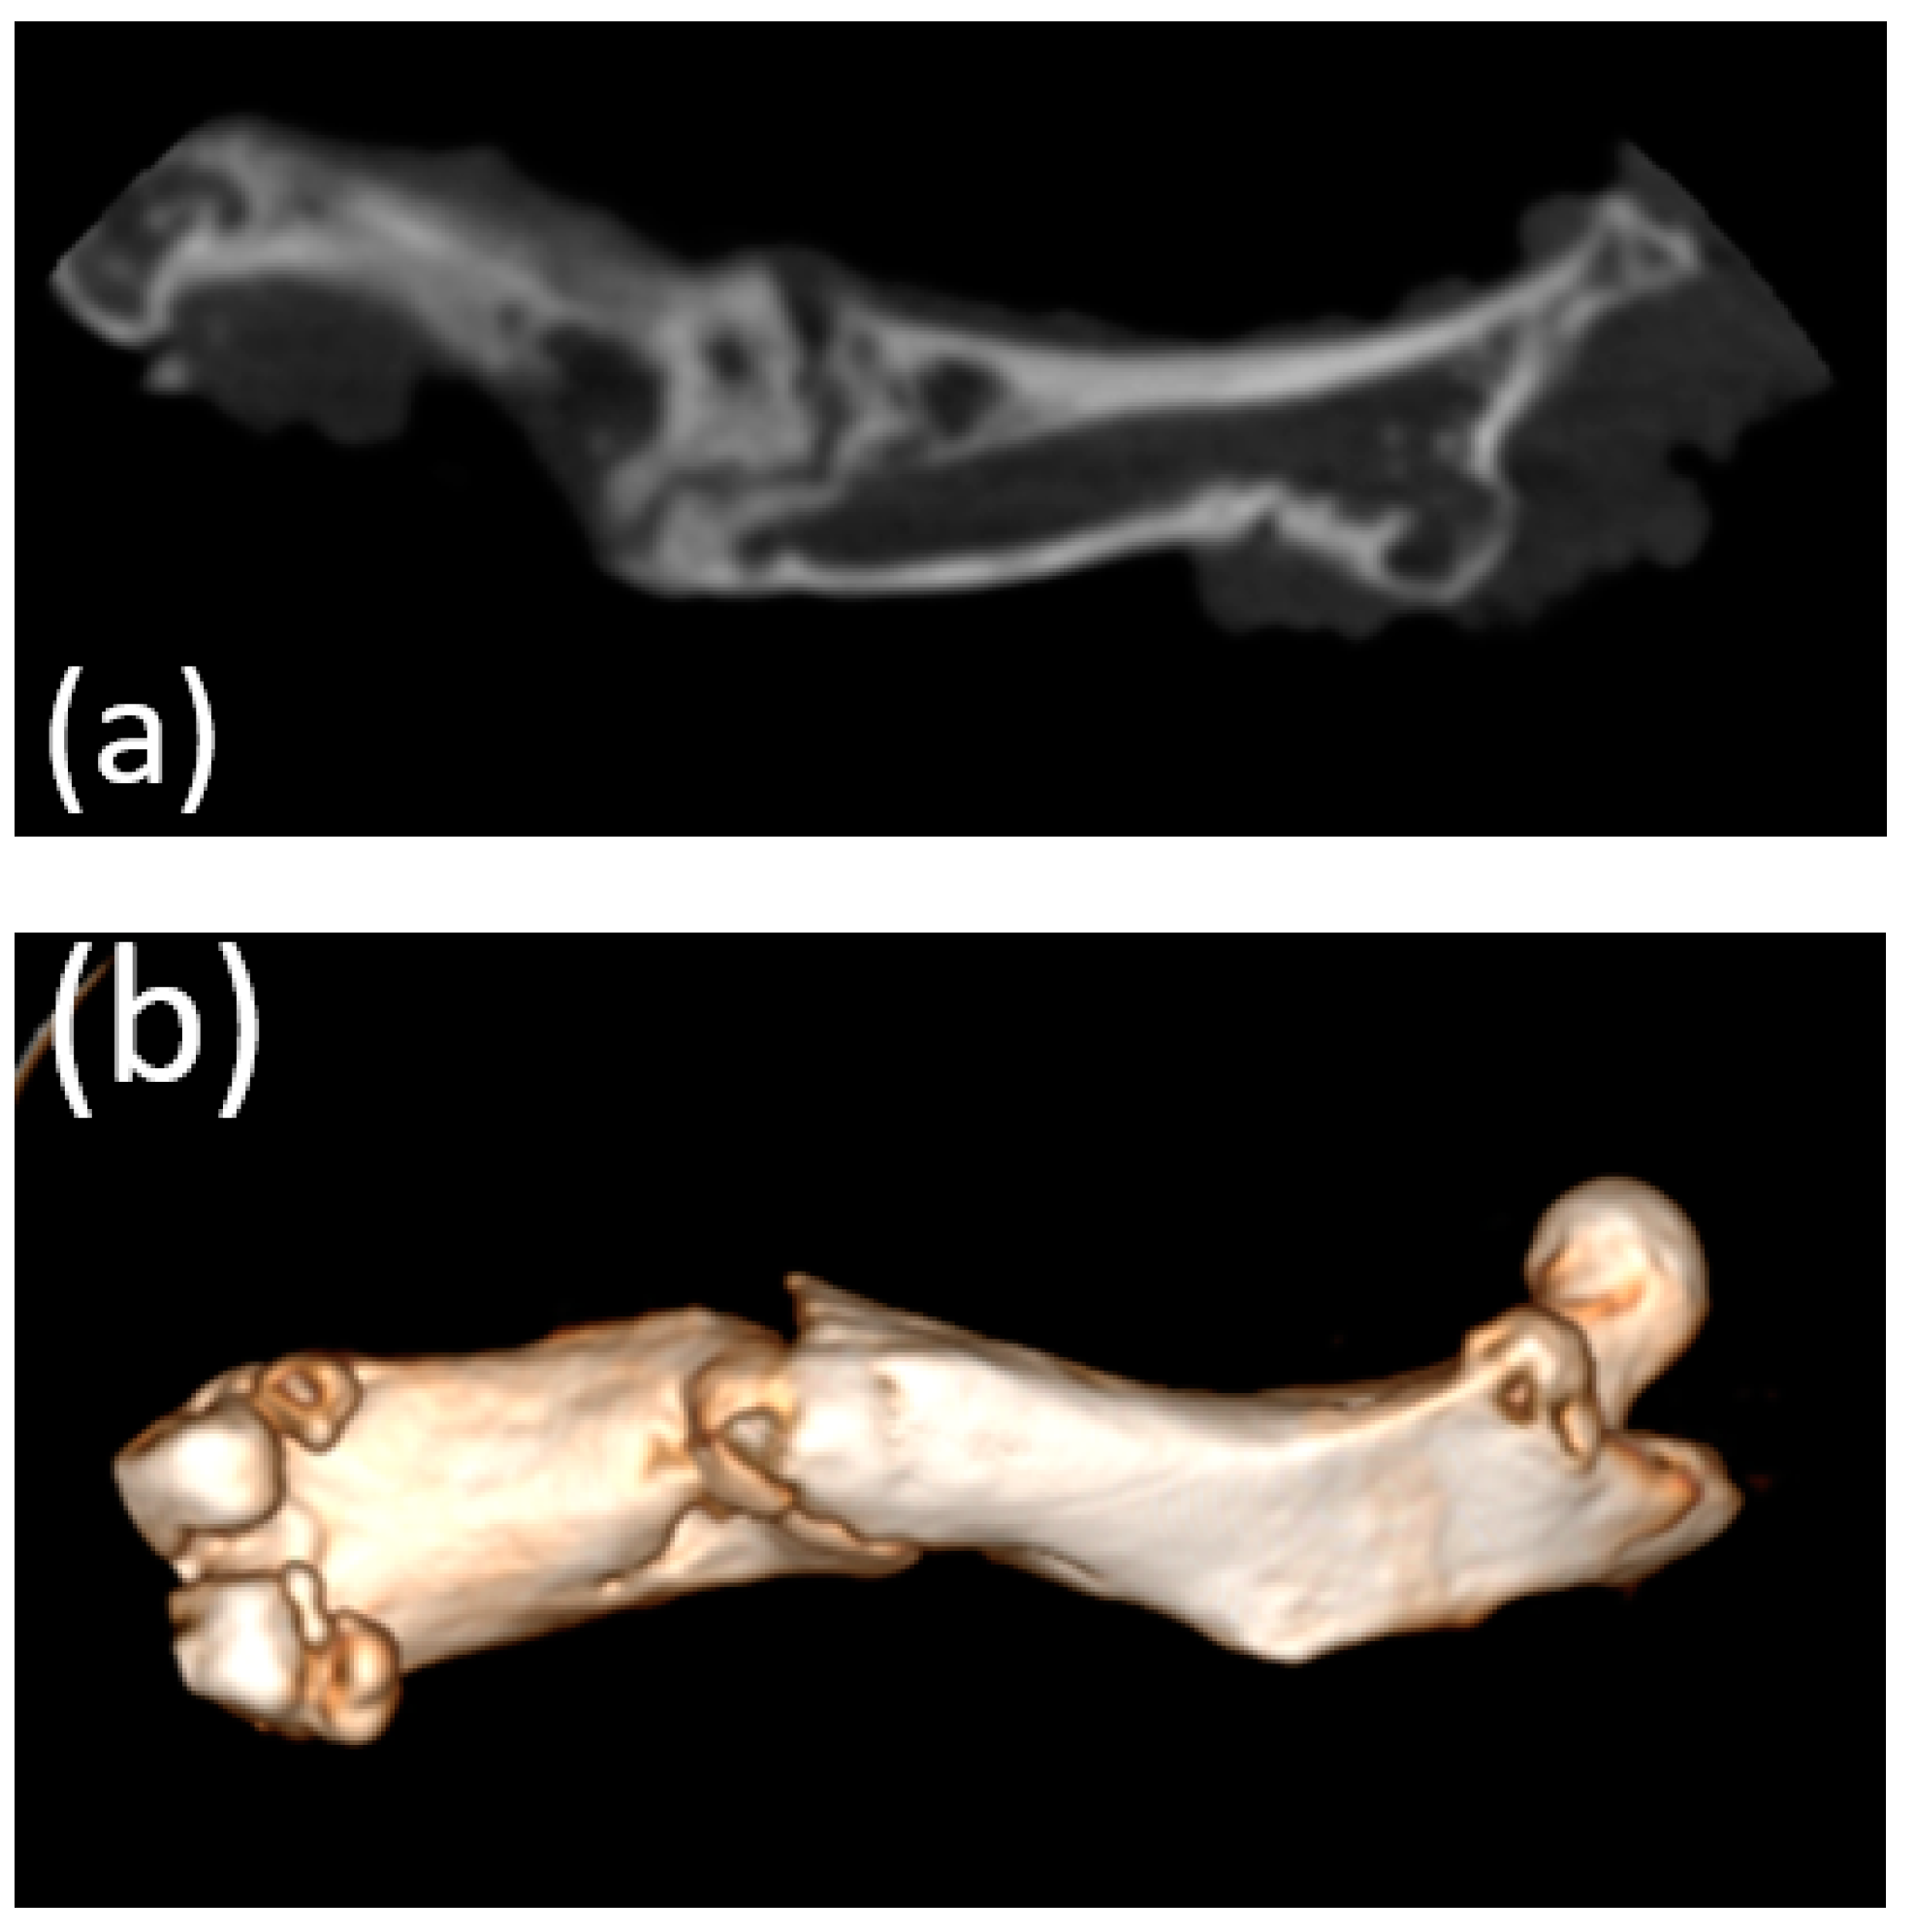

3.4. Cone Beam Computed Tomography

3.5. Micro-CT